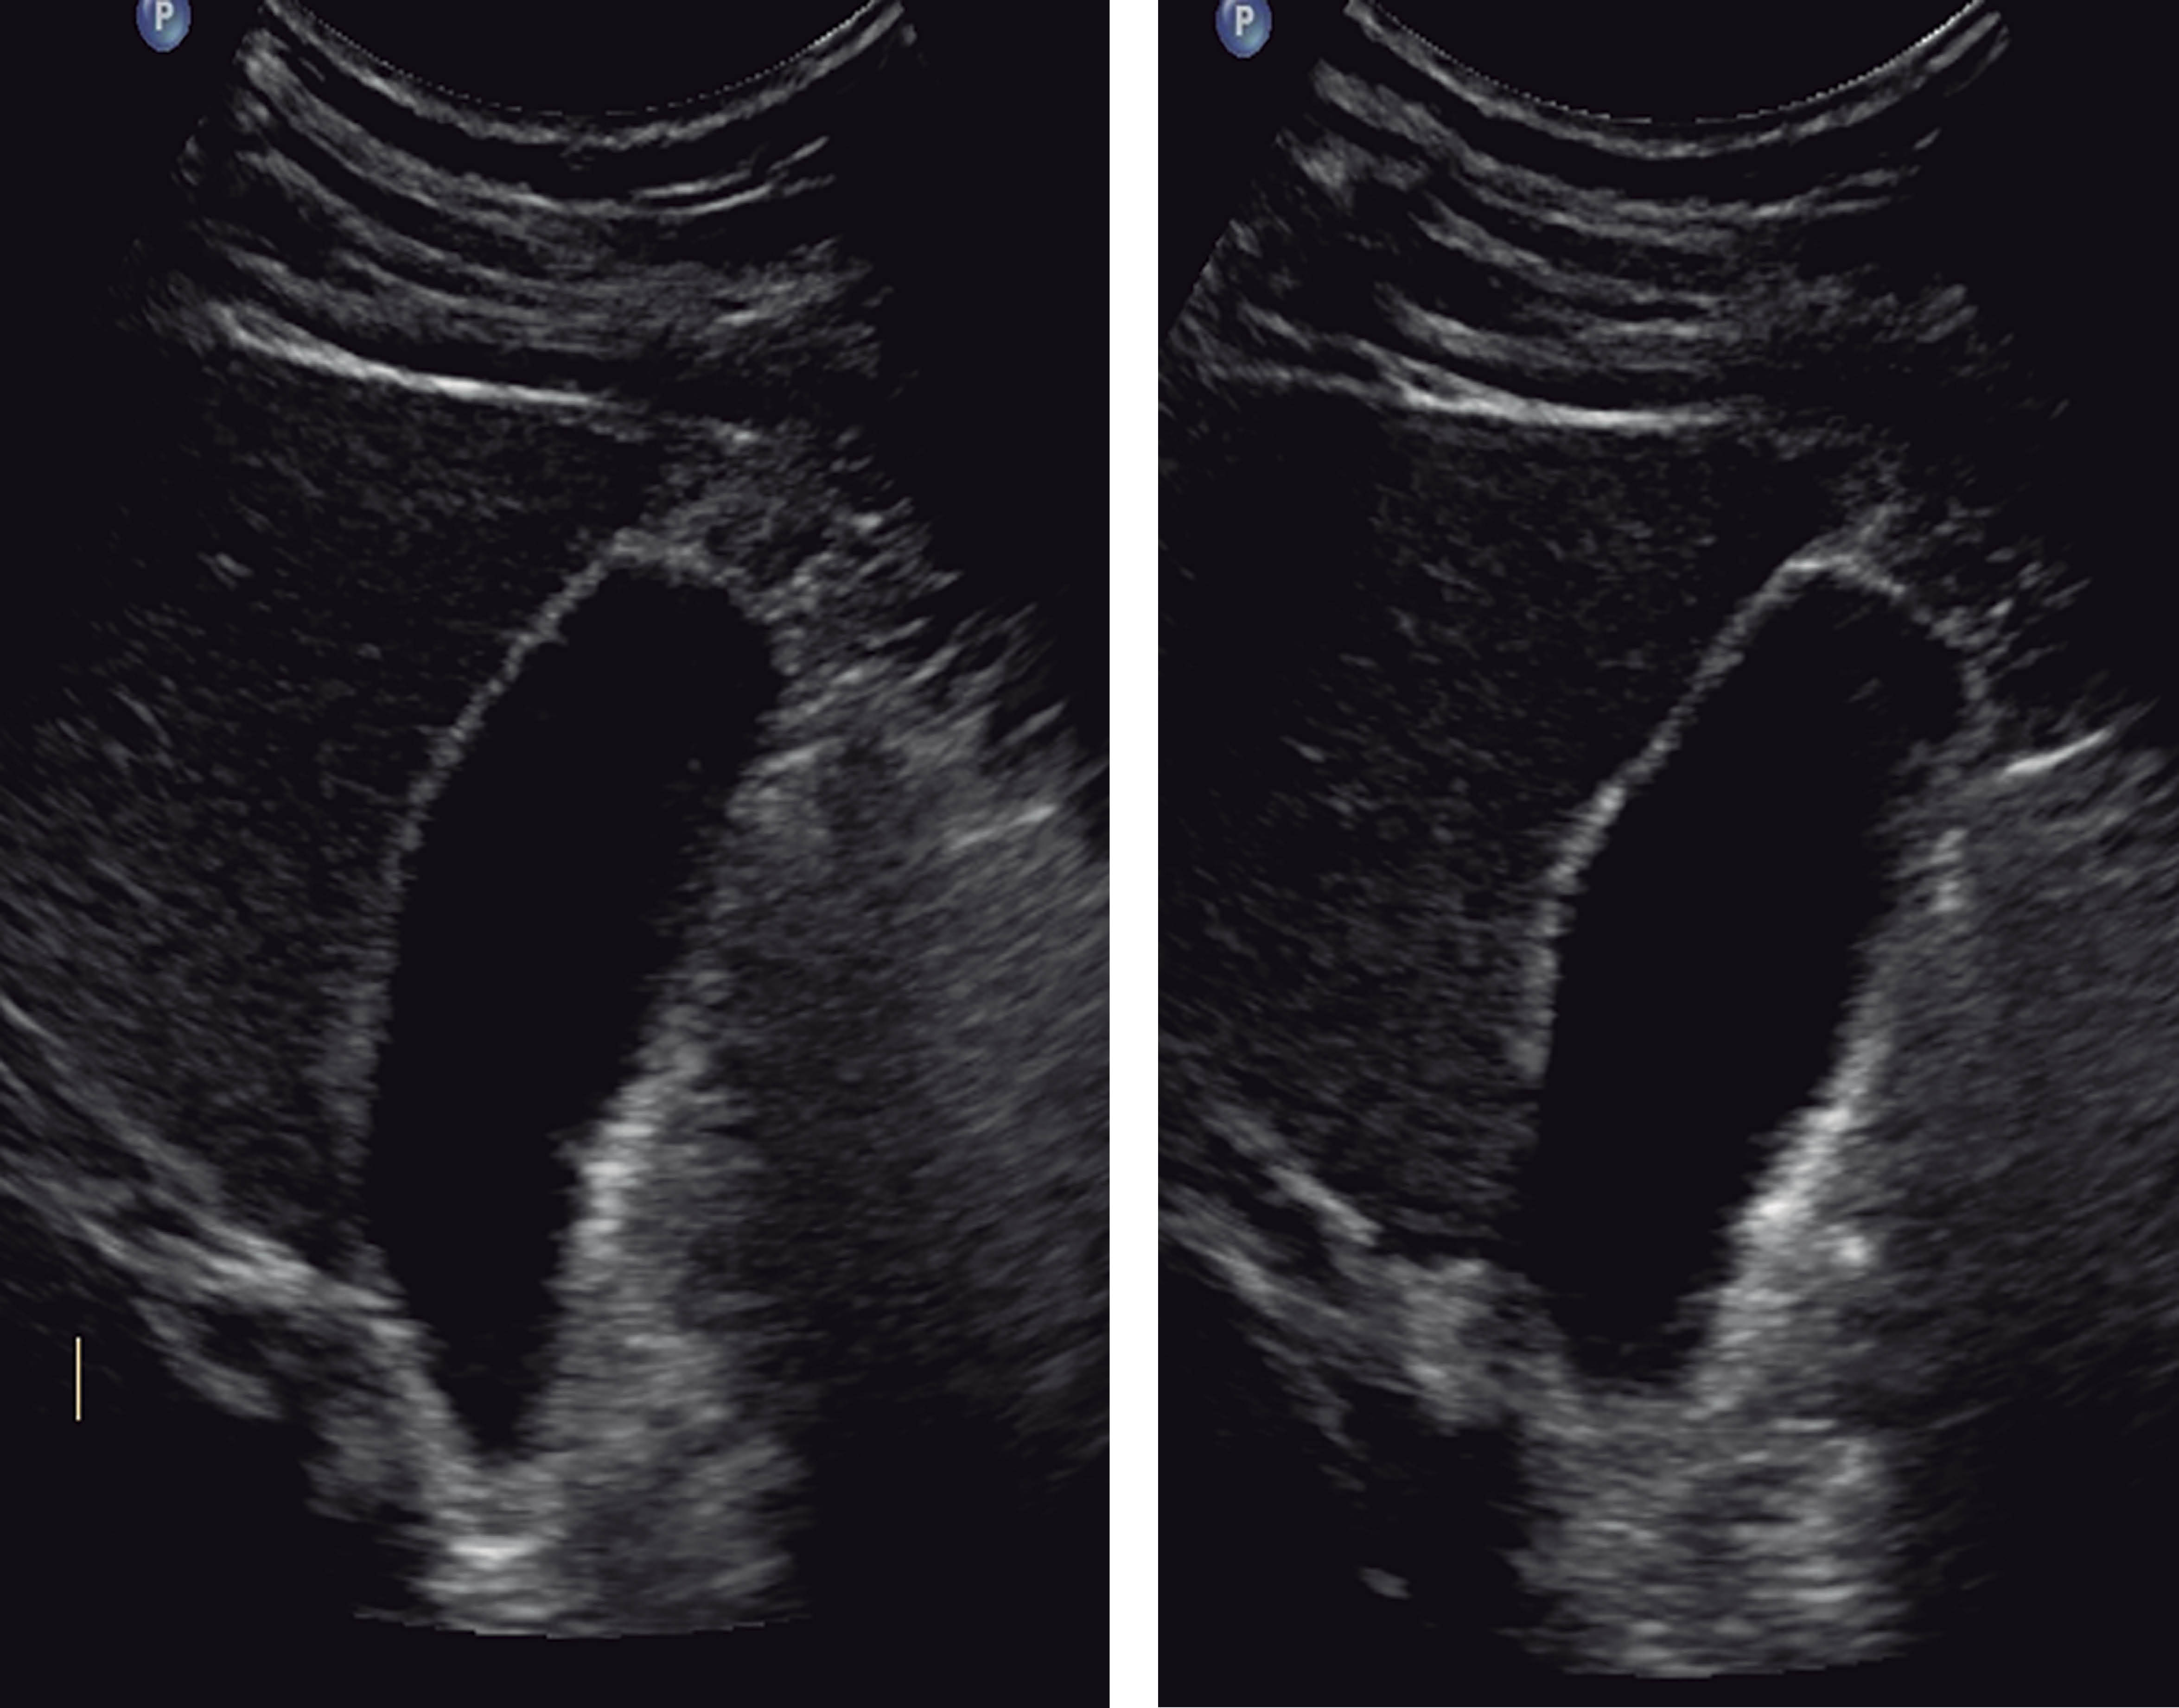

It was decided to continue surveillance and perform a control USG scan 27 hours later. It reported a 60 mm AAST (American Association for the Surgery of Trauma) grade I liver laceration in its longitudinal axis and a gallbladder, as described in Figure 2.

Abdominal ultrasound can be effective by identifying hyperechogenic content in the gallbladder, peri vesicular free fluid, and continuity solution of the gallbladder wall. A hypoechoic, thickened edematous gallbladder wall despite prolonged fasting correlates with acute cholecystitis.4